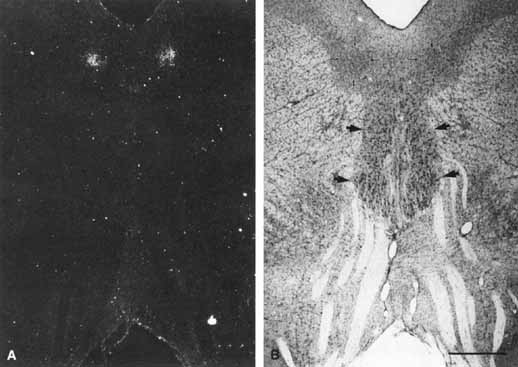

monkey (Macaca mulatta): Evidence for sensorimotor links

to the thalamus and oculomotor nuclei. Brain Res 127:197, 1977 14. Burde RM: The visceral nuclei of the oculomotor complex. Trans Am Ophthalmol Soc 81:532, 1983 15. Warwick R: Representation of the extra-ocular muscles in the oculomotor complex. J Comp Neurol 98:449, 1953 16. Jampel RS, Mindel J: The nucleus for accommodation in the midbrain of the macaque. Invest Ophthalmol 6:40, 1967 17. Burde RM, Loewy AD: Central origin of the oculomotor parasympathetic neurons in the monkey. Br Res 198:434, 1980 18. Kourouyan HD, Horton JC: Transneuronal retinal input to the primate Edinger–Westphal nucleus. J Comp Neurol 381:68, 1997 19. Warwick R: The ocular parasympathetic nerve supply and its mesencephalic sources. J Anat 88:71, 1954 20. May PJ, Fratkin JD: Identification of the Edinger–Westphal nucleus in primates by means